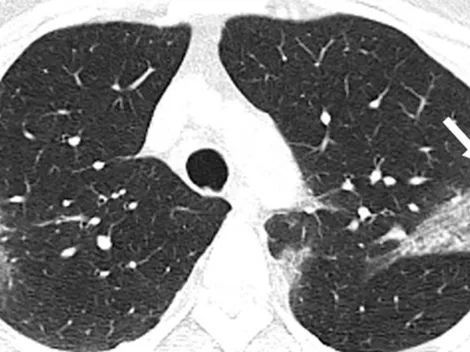

La Sociedad de Radiología de Norteamérica publicó un video que muestra los efectos del Coronavirus en los pulmones.